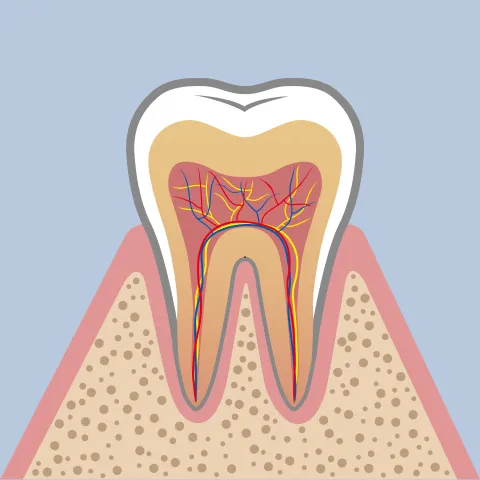

歯周病とは、歯を支える「歯ぐき」や「歯槽骨(しそうこつ)」といった土台の組織が、細菌によって徐々に破壊されていく病気です。

歯をしっかりと支えているのは、目に見えない部分にある「歯槽骨」という骨です。